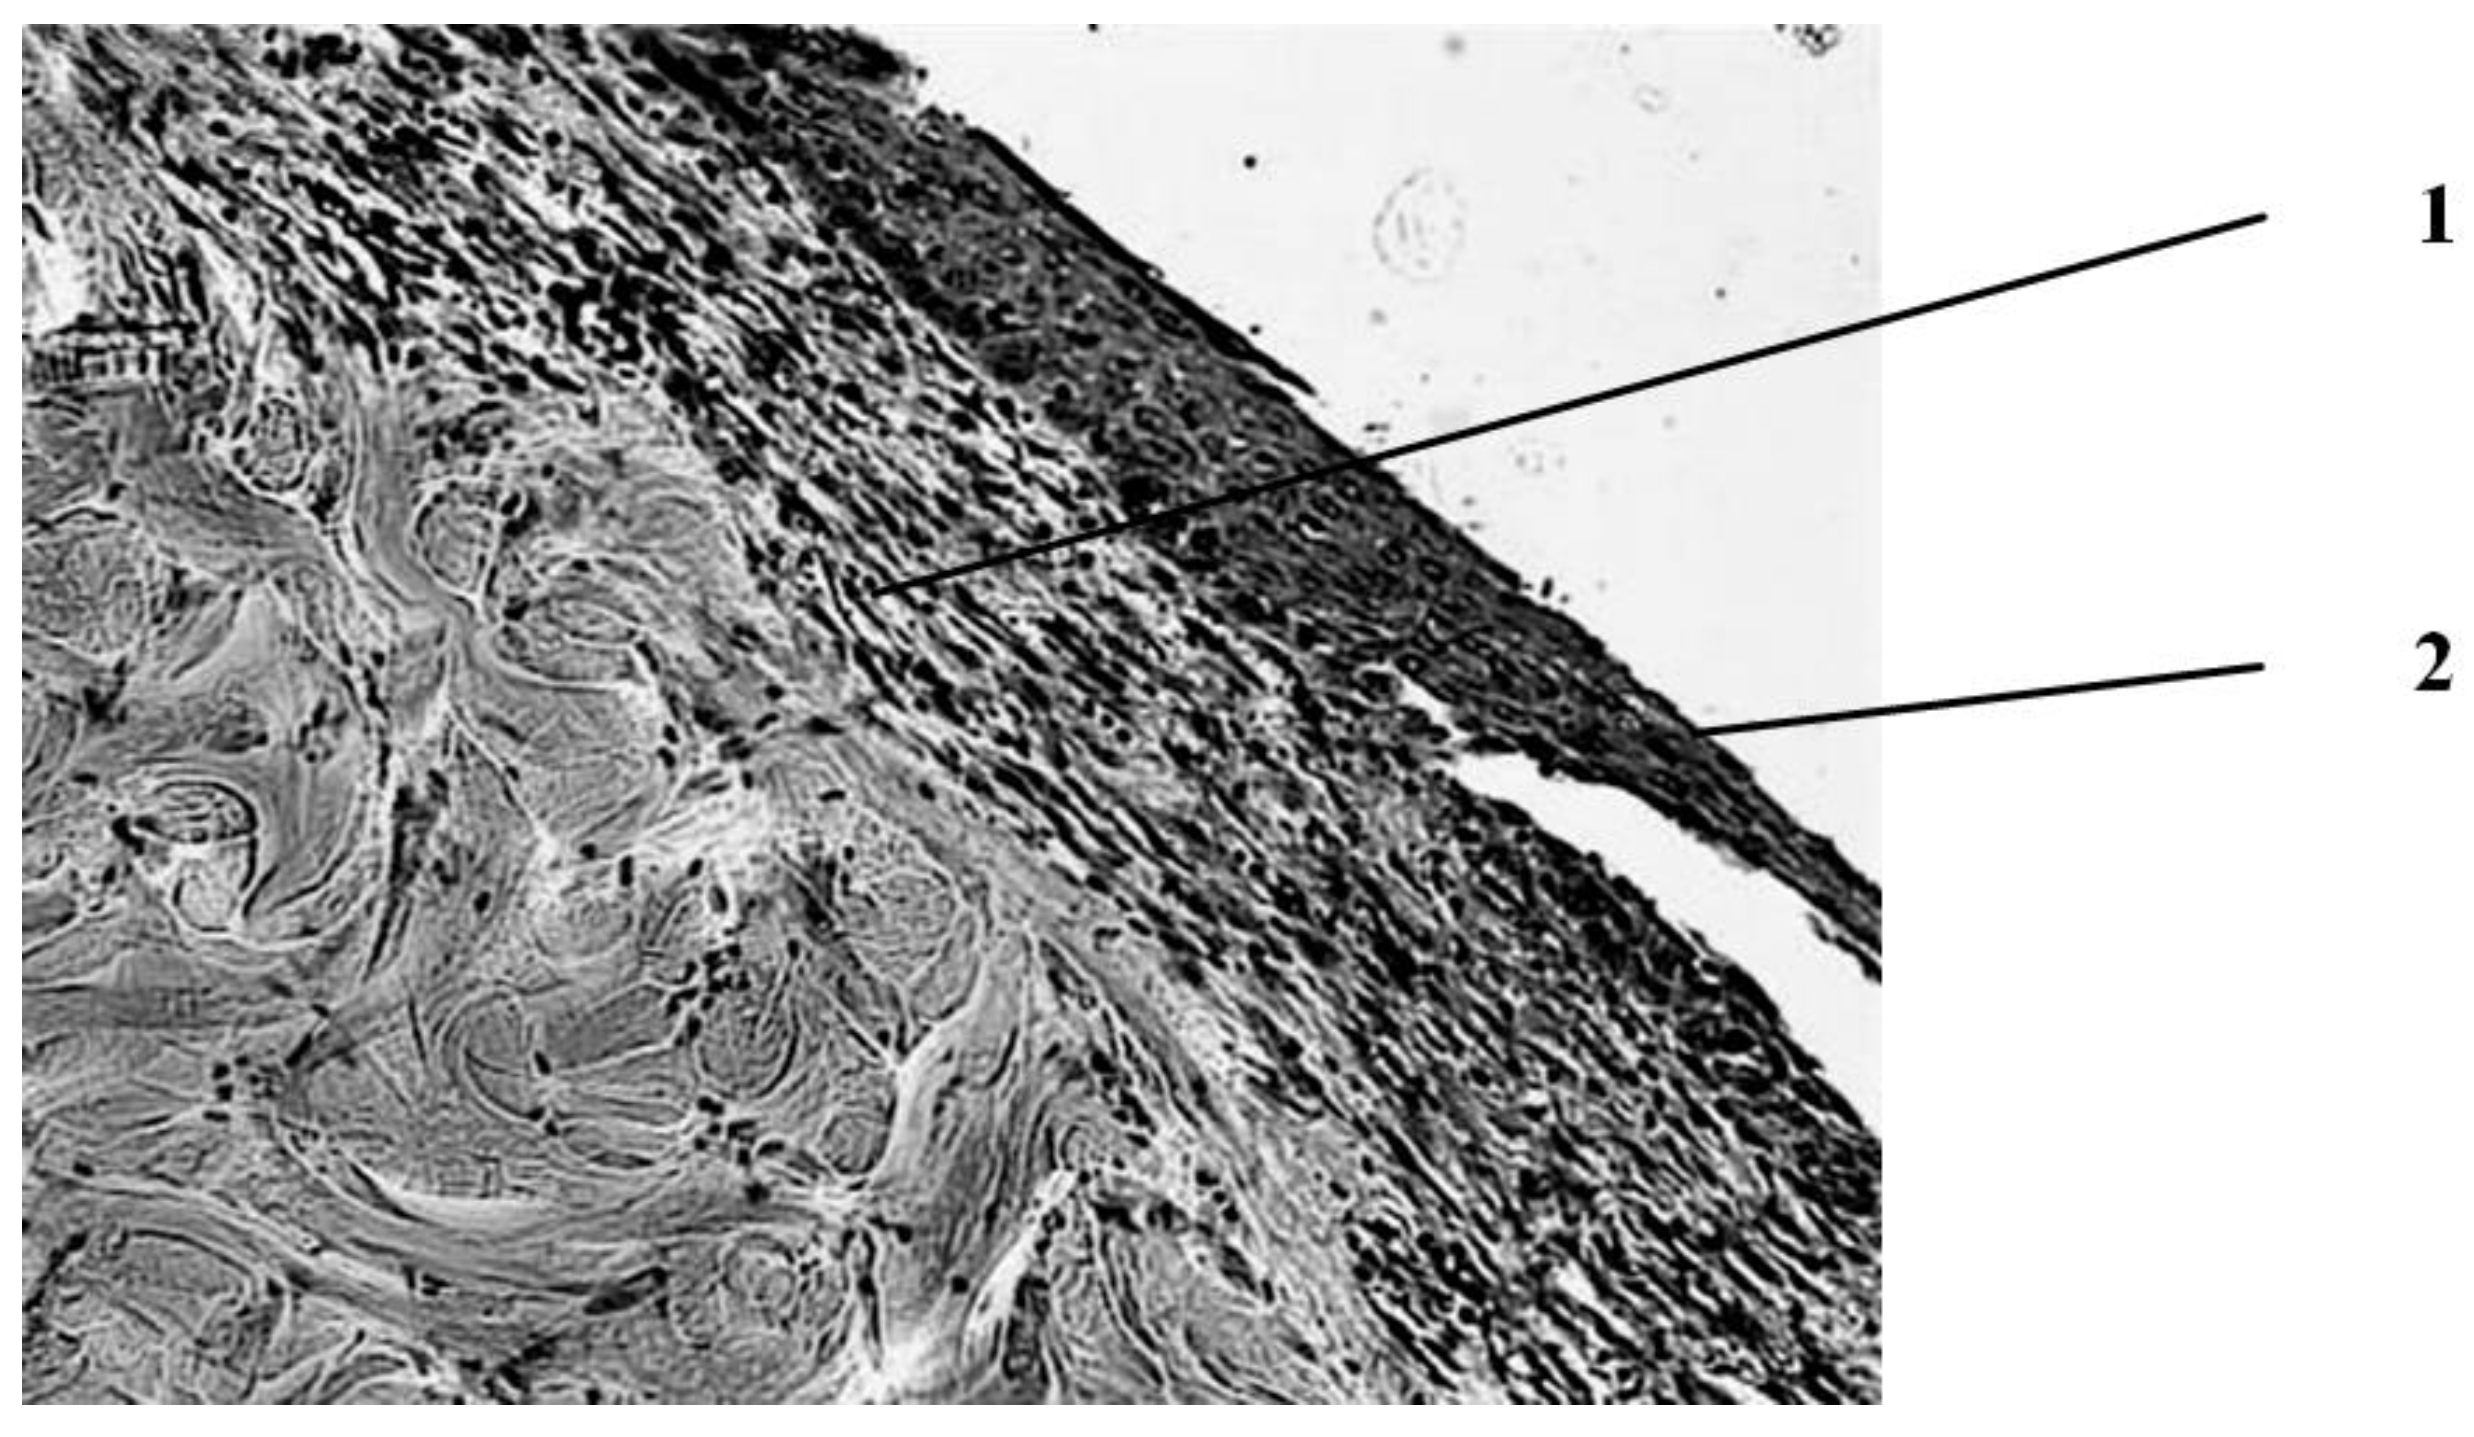

According to the results of histological examination, it was found that the first day after the injury, the histological picture in the edges of wounds in animals of all three groups had no differences (Figure 1). In all preparations, there is a lesion of the epidermis (necrosis and necrobiosis), dermis (papillary and mesh layers), manifested by the loss of the usual fibrous structure of the connective tissue of the dermis and transformation collagen fibers into a solid homogeneous mass, as well as edema and hemorrhages in loose connective tissue and adipose tissue located above the layer of the skin’s own muscle.

The blood vessels passing through here are often also necrotic, containing red blood clots. The muscle fibers of the skin’s own muscles are in a state of dystrophy: swollen, often vacuolated. There are no cores in individual fibers. In the loose connective tissue located under the muscle layer, there is fullness, puffiness, as well as an increased number of cells, among which leukocytes and macrophages predominate.

Figure 1. Histological picture of the wound on the first day after the burn (typical picture for rats of all groups). Deep burn with necrosis of the epidermis, papillary and mesh layers of the dermis, as well as necrobiosis of the muscle fibers of the skin’s own muscle. Stained with hematoxylin and eosin. magn. ×50.